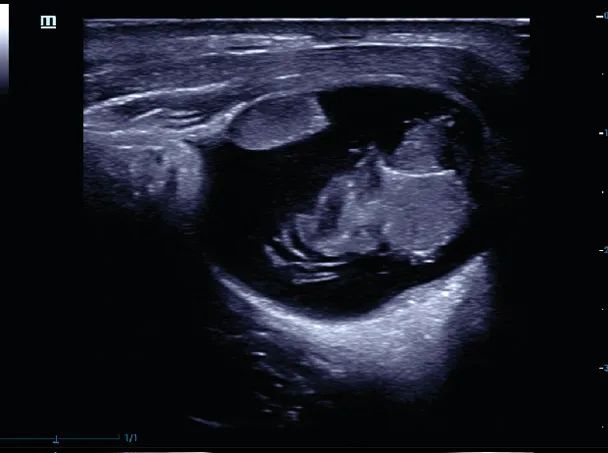

影像图

卵巢